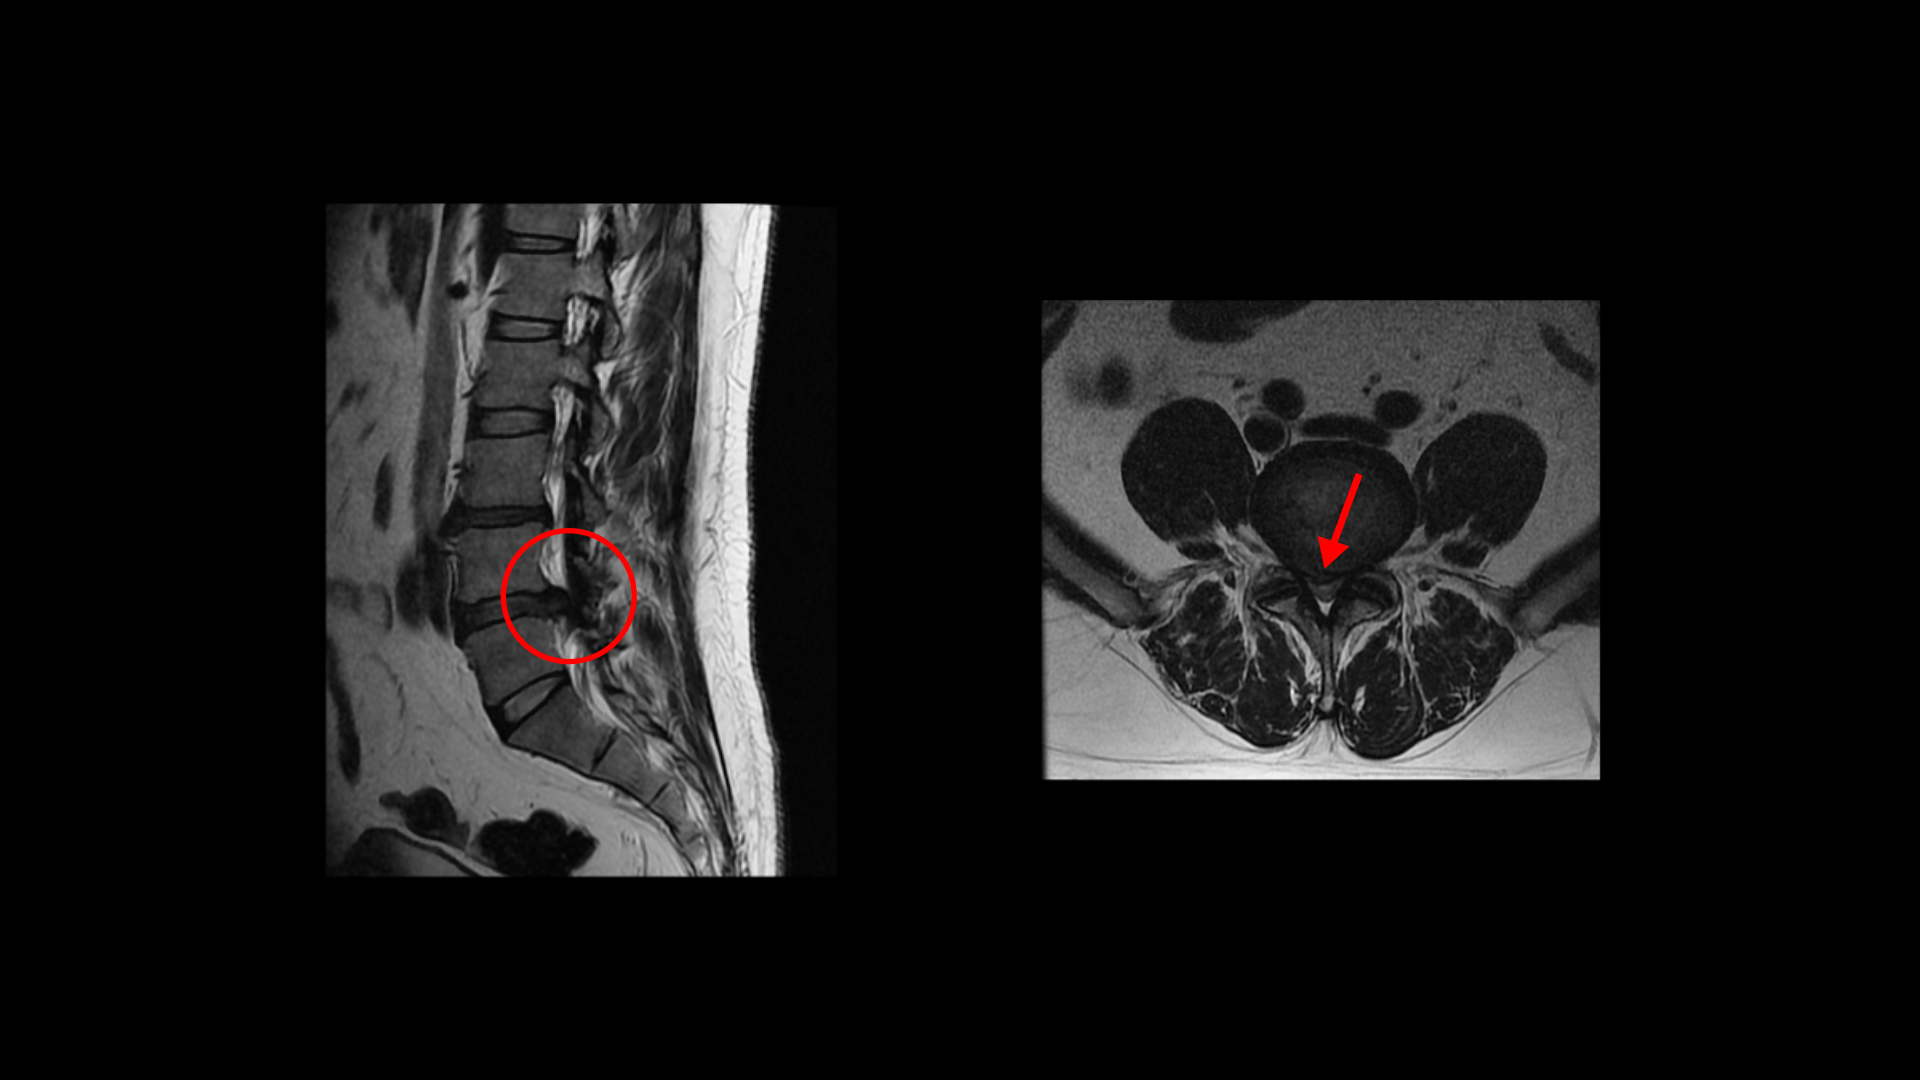

이분 MRI를 보면 4번 5번 마디가 아주 심하게 터져서 우측 중앙으로 밀려 나와 있습니다.